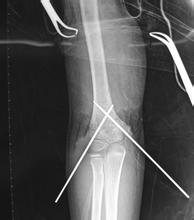

肱骨骨折常发生于肱骨外科颈、肱骨干、肱骨髁上、肱骨髁间、肱骨外髁、肱骨内上髁。其中,尤以前三者为多,可发生于任何年龄,多由直接暴力和间接暴力所引起,如重物撞、

挤压、打击及扑倒时,手或肘部着地,暴力经前臂或肘部传至各部位。X线检查可明确诊断,并提示骨折的类型。

肱骨骨折的临床表现主要为肱骨外科颈骨折,局部常出现瘀斑,左上臂纵轴叩击时。

骨折处有锐角,患肢较健侧略短,可出现畸形骨擦音。

肱骨干骨折:患臂肿痛较剧,有明显的压痛,不能握拳,功能丧失,患者常将前臂依附于胸壁。

肱骨髁上骨折:肘部肿胀疼痛,甚至出现张力性水疱,肩部压痛甚剧,肘关节功能丧失,骨折部位有异常活动和骨擦音。